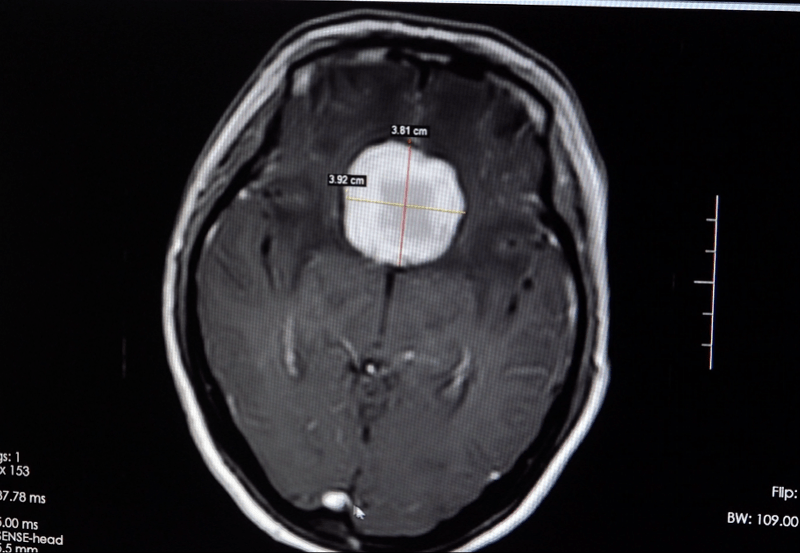

该院接诊的副院长鲁明仔细查看患者的影像资料 , 结合症状 , 认为是鞍区脑膜瘤的可能性较大 , 遂将患者收治入神经外五科 。 患者入院后 , 神经外五科主任欧阳辉教授组织全科进行认真讨论 , 反复研究手术方案 。 完善术前准备后 , 神经外五科团队为患者实施鞍区脑膜瘤切除术 , 顺利切除了一个41mmX37mmX27mm宛如鸡蛋大小的肿瘤 。